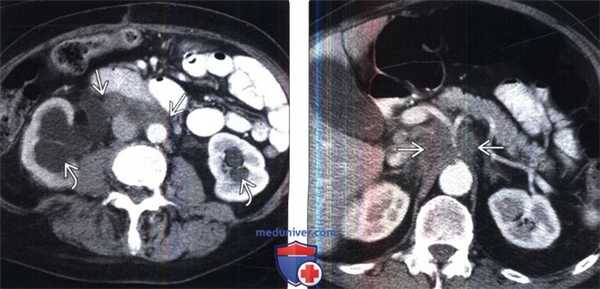

2. КТ при ретроперитонеальной и мезентериальной лимфоме:

• КТ с контрастированием:

о Увеличенные узлы (обычно более 1 см в наименьшем размере) для мезентериальных и парааортальных лимфатических узлов:

- Ретрокруральные лимфатические узлы считают увеличенными при размере более 6 мм

о Сплошная мягкая ткань может окружать сосуды брыжейки и аорту/НПВ

о Смещение аорты от позвоночника (нехарактерно для доброкачественного процесса)

о Контрастирование лимфатических узлов, плотность которых приближена в мышечной

о У пациентов при отсутствии лечения редко происходит кальцификация лимфатических узлов (менее 1%) или кистозное перерождение

о Узлы при НХЛ, как правило, больше, чем ЛХ:

- Для лимфатических узлов при НХЛ также более характерно фрагментированное распределение

- Мезентериальную лимфаденопатию чаще встречают при НХЛ (более 50%), чем при ЛХ (менее 5%)

о При НХЛ перипанкреатическиелимфатическиеузлы могут имитировать опухоль поджелудочной железы

о У 25% больных с впервые выявленной ЛХ вовлечены парааортальные лимфатические узлы по сравнению с 50% при НХЛ

о ЛХ: как правило, в начальной стадии вовлечены верхние парааортальные лимфатические узлы с отсутствием непораженных участков

о При ЛХ лимфатические узлы могут быть нормальных размеров, но при этом содержат микроскопическую опухоль, что приводит к ложноотрицательному результату при КТ

(Слева) УЗИ, поперечная плоскость: визуализировано мягкотканное образование, окружающее аорту и НВП при НХЛ.

(Справа) Бесконтрастная КТ, аксиальная проекция (этот же пациент): пораженные лимфатические узлы при НХЛ заполняют парааортальное пространство и смещают аорту от позвоночника.